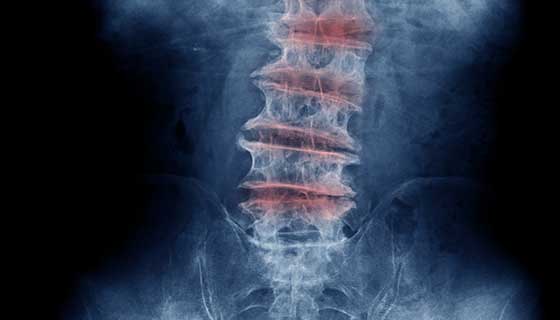

Thoái hóa khớp là tình trạng sụn bảo vệ đệm các đầu xương bị thoái hóa hoặc mòn đi. Điều này gây ra sưng và đau. Nó cũng có thể gây ra sự phát triển của gai xương. Tương tự, thoái hóa cột sống là tình trạng tổn thương sụn khớp và đĩa đệm ở cổ và thắt lưng. Đôi khi, thoái hóa khớp tạo ra các gai gây áp lực lên các dây thần kinh rời khỏi cột sống. Điều này có thể gây ra yếu và đau ở cánh tay hoặc chân. Như vậy gai cột sống và thoái hóa cột sống là một bệnh nhưng hai thuật ngữ với hai hàm ý khác nhau: Thoái hóa cột sống chỉ cấu trúc của cột sống đang bị thoái triển còn gai cột sống dùng để chỉ những người bệnh thoái hóa cột sống đã phát triển những gai xương thường thấy trên X-quang.

Cách tốt nhất để xác nhận chẩn đoán thoái hóa cột sống là chụp X-quang. Bác sĩ sẽ hỏi bệnh sử và khám thực thể để xem người đó có bị đau, nhức, mất cử động liên quan đến cổ hoặc lưng dưới hay không, hoặc nếu các triệu chứng gợi ý, các dấu hiệu liên quan đến thần kinh như yếu, thay đổi phản xạ, hay mất cảm giác. Bác sĩ có thể yêu cầu một số xét nghiệm nhất định để hỗ trợ chẩn đoán thoái hóa khớp cột sống như: